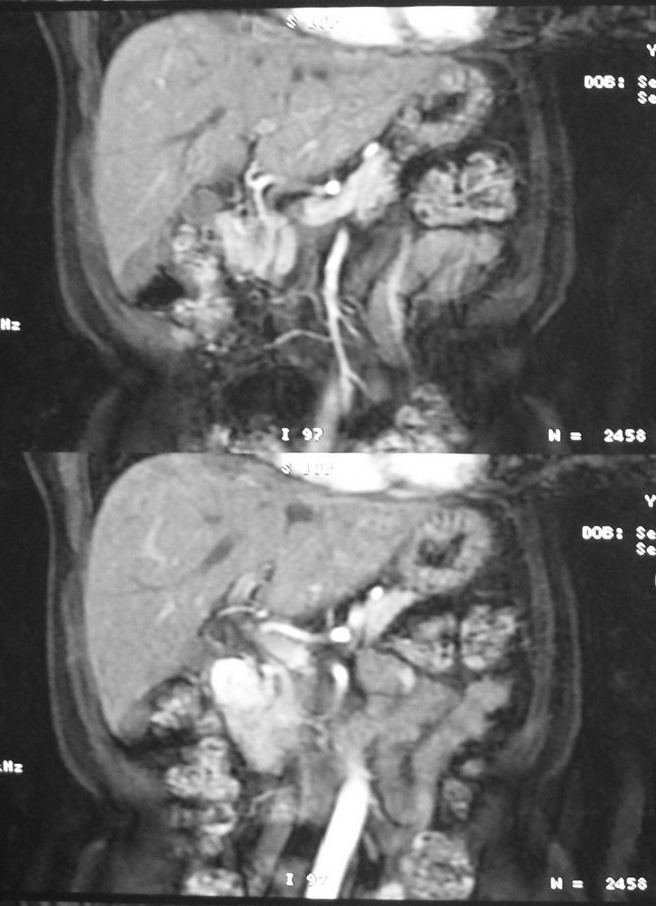

标题: MRI2066:腹膜后占位,请会诊,CT18531近期扫描图像

无明显不适,体检发现,

mri基本排除血管类肿瘤,明显强化说明极富血供,临床无症状,考虑胰岛细胞瘤可能大。

强化明显,并见有血管与之相连;考虑巨淋巴增生症.

极富血供的占位性病变,首先考虑良性,期待结果。